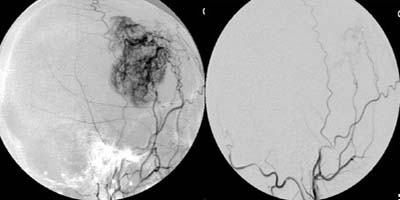

<³úÁöÁÖ¸·ÇÏÃâÇ÷>

<¼ö¼ú

Àü>

³úµ¿¸Æ·ù¿¡

ÀÇÇÑ ÁöÁÖ¸·ÇÏÃâÇ÷ÀÇ CT¼Ò°ß ¹× Ç÷°üÁ¶¿µ¼ú¿¡¼

Àü±³Å뵿¸Æ¿¡ µ¿¸Æ·ù°¡ º¸À̰í ÀÖ´Ù.

Àå¸é> <¼ö¼ú

ÈÄ>

¼ö¼ú

ÈÄ µ¿¸Æ·ù°¡ º¸ÀÌÁö ¾ÊÀ¸¸ç µ¿¸Æ·ù °æºÎ¿¡

Ŭ¸³ÀÌ µé¾î°¡ ÀÖ´Â °ÍÀÌ º¸À̰í

ÀÖ´Ù.